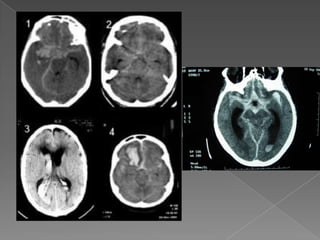

HEMORRAGIA INTRACEREBRAL Localización. Lobar

HEMORRAGIA INTRACEREBRAL Localización Ganglionar

HEMORRAGIA INTRACEREBRAL Localización Tallo: puente Cerebelo